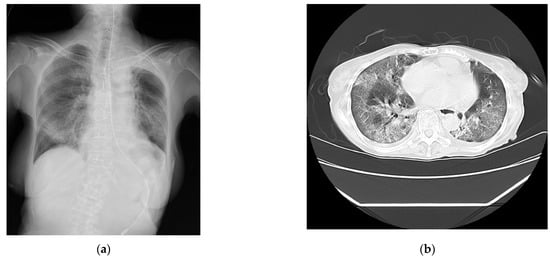

The laboratory test findings of Case 1 indicated that the inflammatory marker and brain natriuretic peptide levels were moderately to highly elevated. The chest radiographs (Figure 1a) and computed tomography images (Figure 1b) showed extensive ground-glass opacities and a crazy-paving pattern. The 24 h Holter electrocardiography performed upon admission showed that all AECG-Ms were positive (Table 4; Figure 1c–e).

Figure 1.

The findings for Case 1. (a) The chest radiograph captured on the day of admission. (b) The chest computed tomography image captured on the day of admission showing bilateral diffuse ground-glass opacities. (c) An analysis of the LPs measured using high-resolution 24 h Holter electrocardiography on the day after admission. The filtered QRS duration (fQRS) was 128 milliseconds, the root-mean-square voltage of the signals (RMS40) was 4.4 μV (<20 μV), and the duration of the low-amplitude signal after the voltage decreased to less than 40 μV (LAS40) was 60 milliseconds (>38 milliseconds). The patient was determined to be positive. (d) An analysis of the heart rate turbulence (HRT) measured using high-resolution 24 h Holter electrocardiography on the day after admission. The turbulence onset was ≥0%, and the turbulence slope was ≤2.5 milliseconds per RR interval. The patient was determined to have abnormal HRT (Category 2). (e) An analysis of T-wave alternans (TWA) measured using high-resolution 24 h Holter electrocardiography on the day after admission. Shaded in green area indicate the presence of TWA. The TWA was 80.0 μV with a noise level of 10.0 mV. The TWA reference value was 19.9 μV when the noise level was less than 10 mV. The patient was determined to be positive.